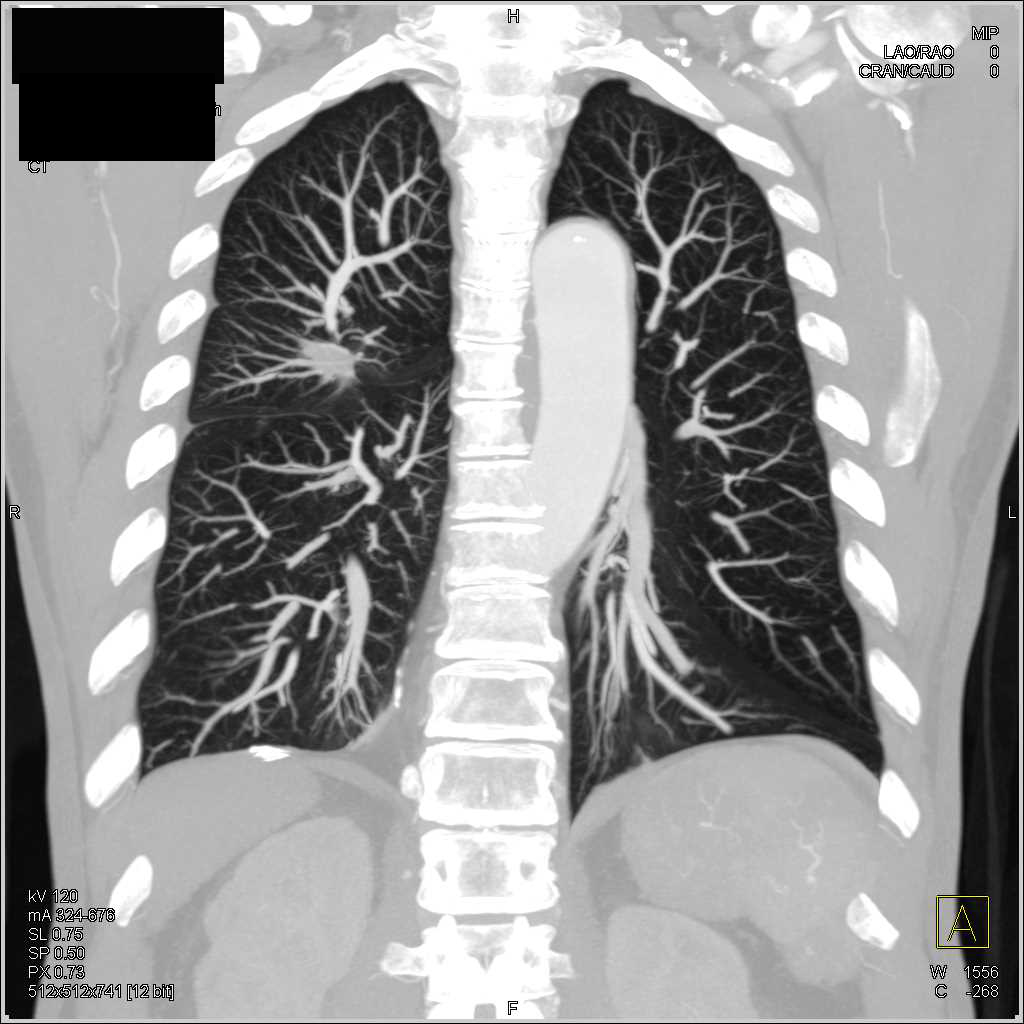

Coronal scan showing scar formation in both right and left lungs Can Lung Scarring Be Seen On An X Ray If you have ipf, doctors listening to your chest can often. It causes lung scarring (tissues scar and thicken over time), making it. Images of the chest may show the scar tissue that is usually part of pulmonary fibrosis. Pulmonary fibrosis is a serious, lifelong lung disease. Can Lung Scarring Be Seen On An X Ray.